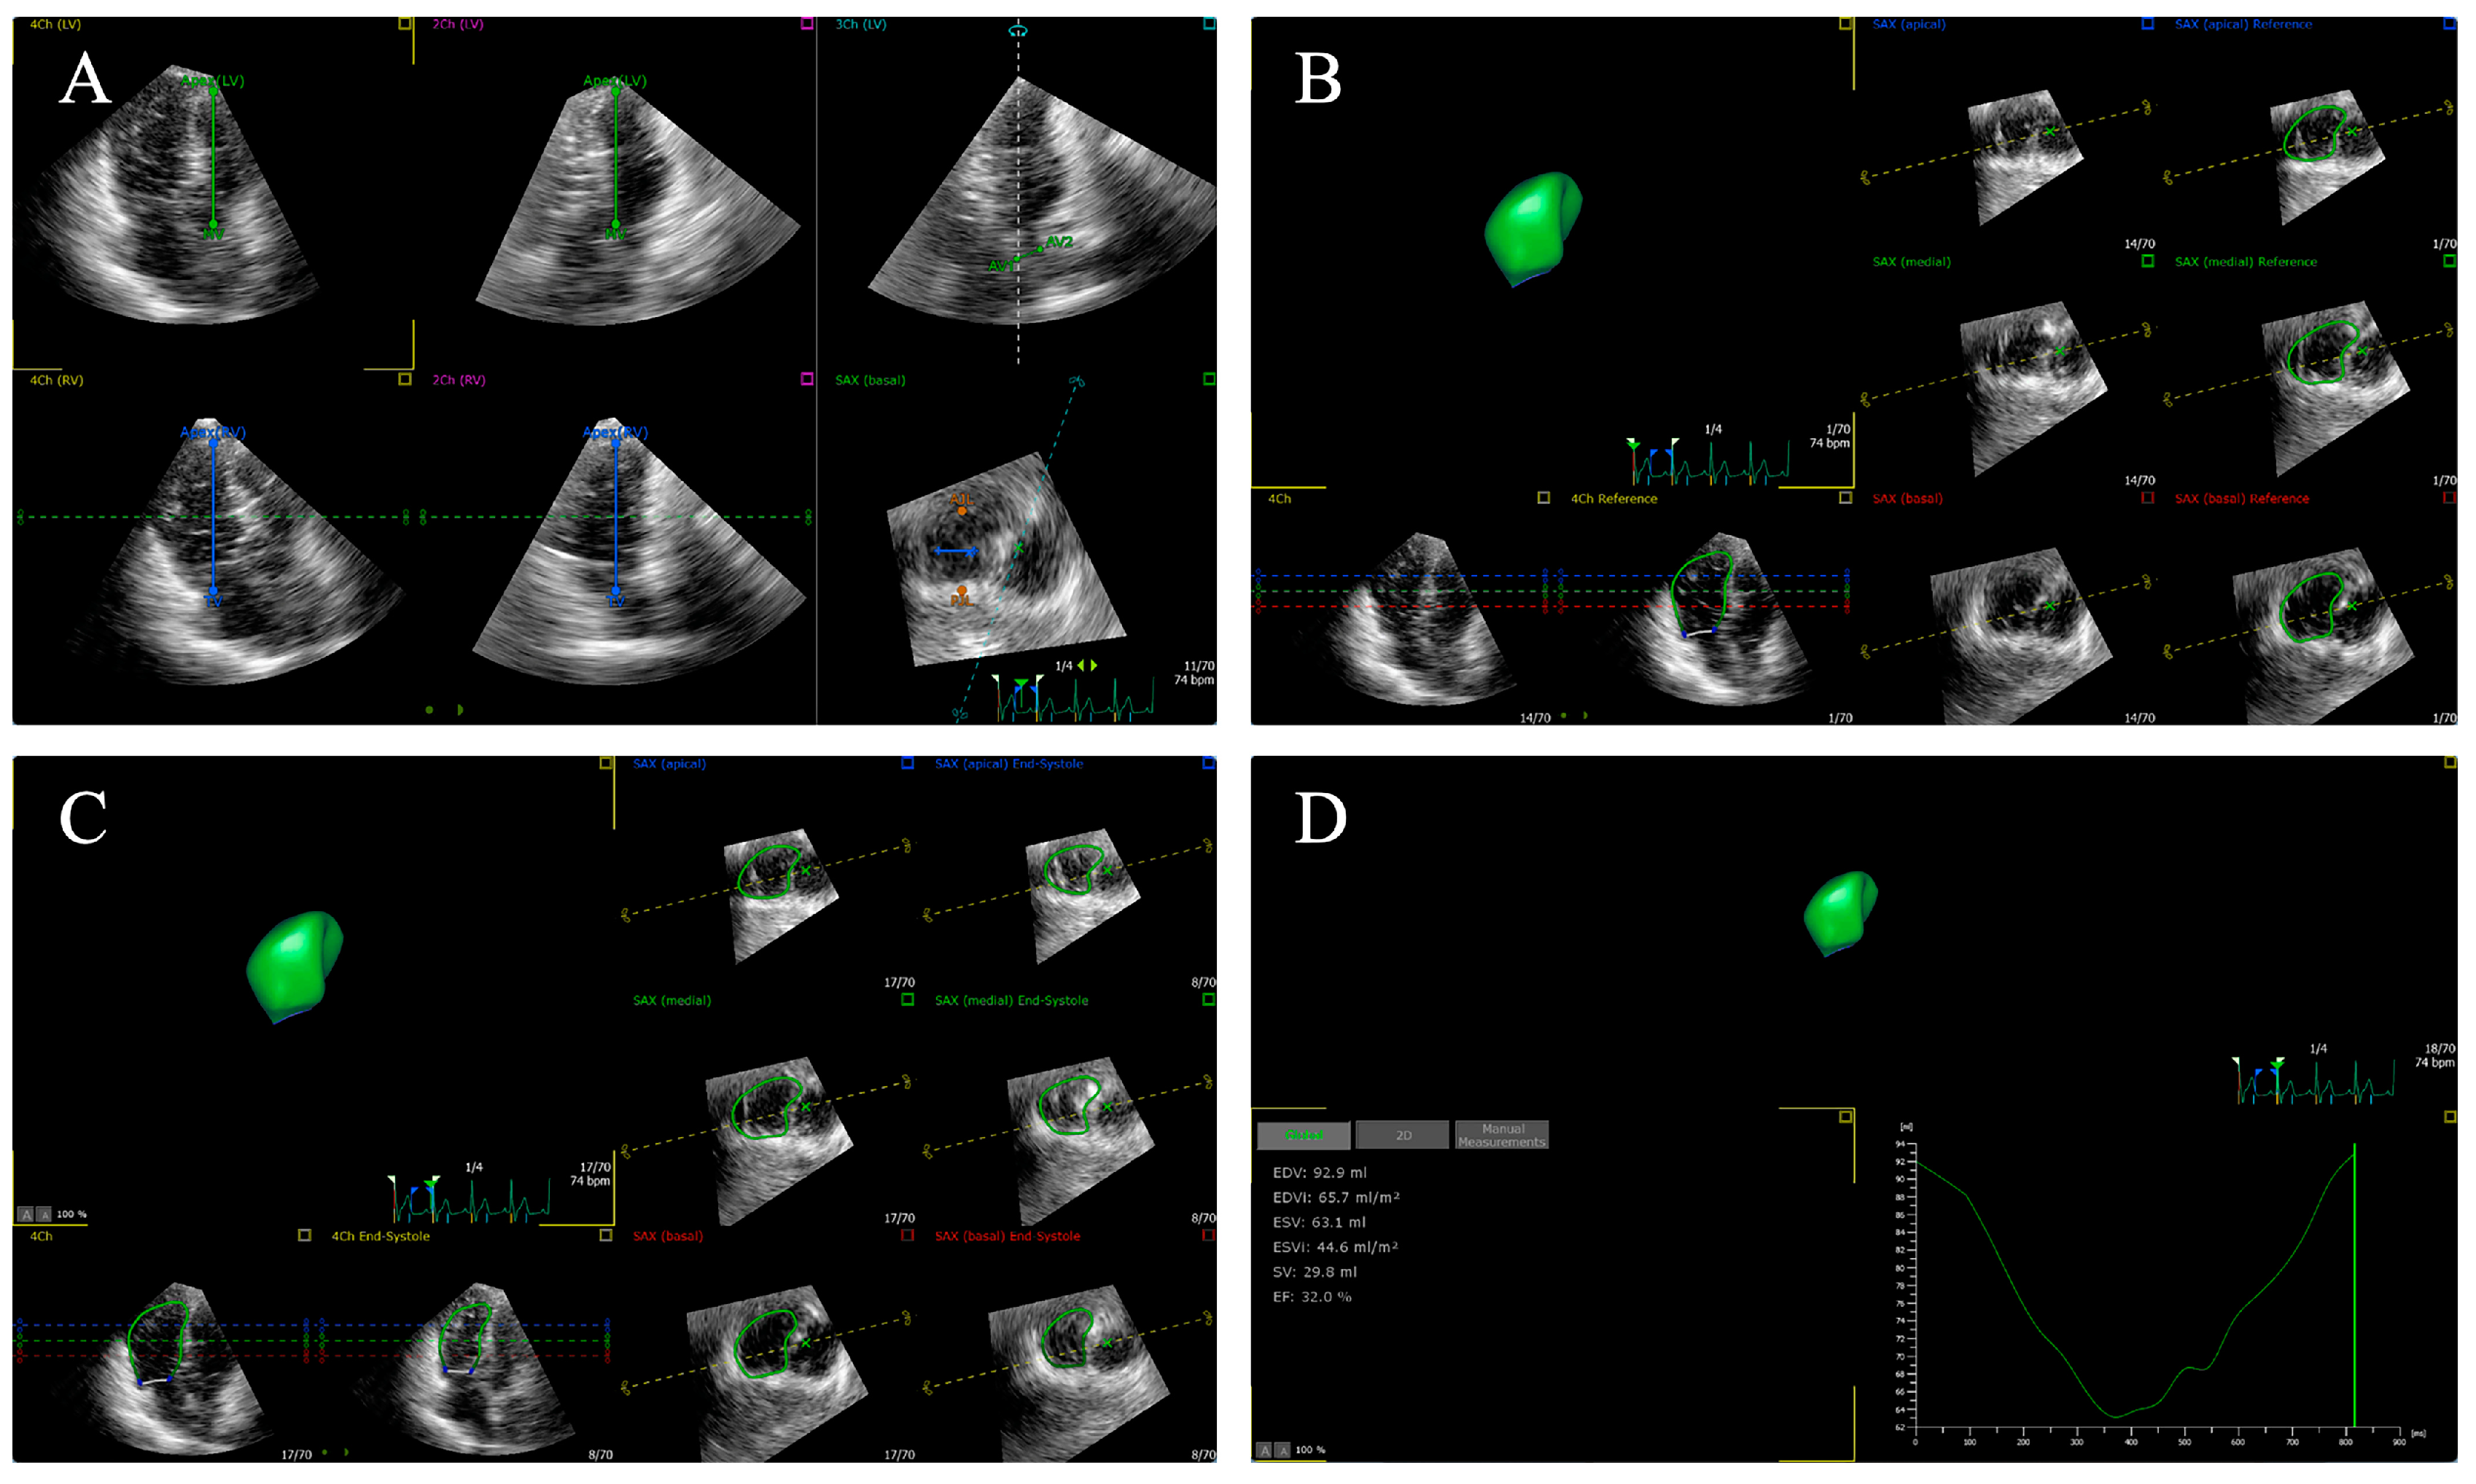

3. Two-Dimensional Echocardiography and Tissue Doppler Imaging

4.3. Two-Dimensional Speckle Tracking Echocardiography

4.4. Three-Dimensional Speckle Tracking Echocardiography